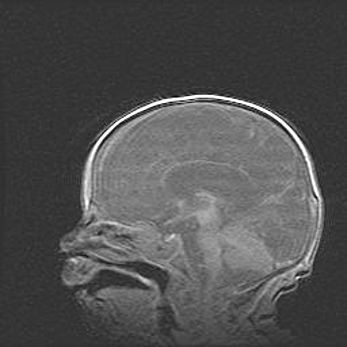

Открытая гидроцефалия.

Возраст: 9 месяцев 12 дней

Вес: 6800 г

Пол: мужской

Окружность головы: 41,5 см

Срок гестации: 28 недель

Гидроцефалия головного мозга у новорожденных имеет характерный признак: опережающий рост окружности головы приводит к визуально хорошо определяемой гидроцефальной форме сильно увеличенного в объёме черепа. Детские неврологи определяют следующие симптомы гидроцефалии у грудничков: выбухающий напряжённый родничок, частое запрокидывание головы, смещение глазных яблок к низу.